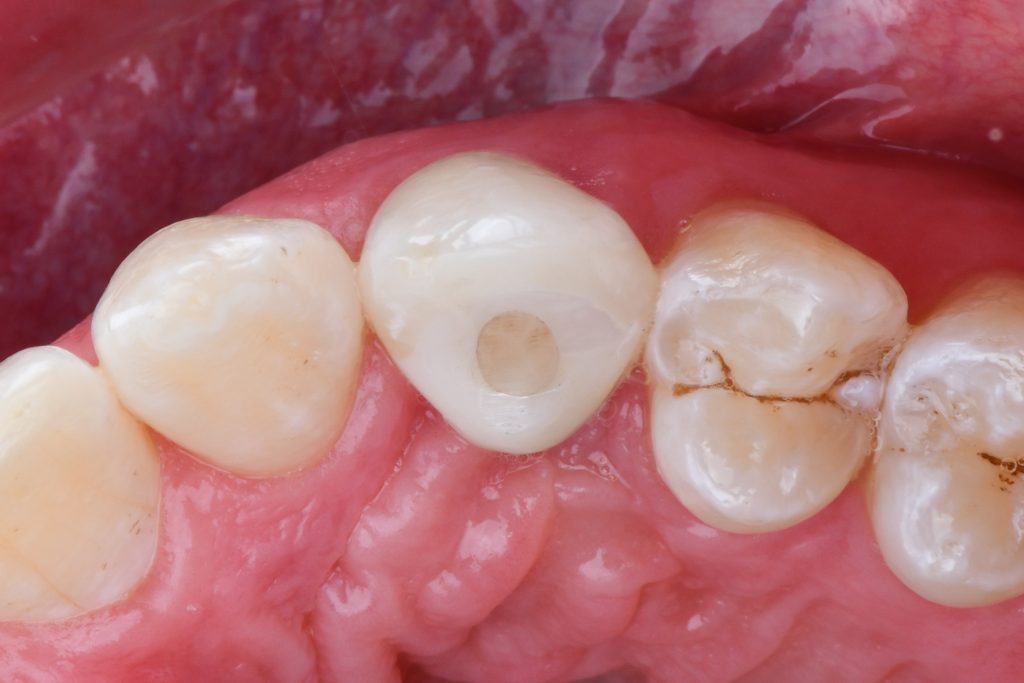

emergence profile trained by a temporary crown

full ceramic crown on a Variobase abutment